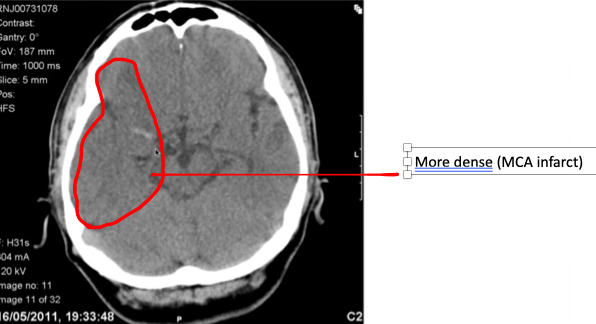

Ischaemic stroke

Which artery is affected in this ischaemic stroke [1]

A

MCA